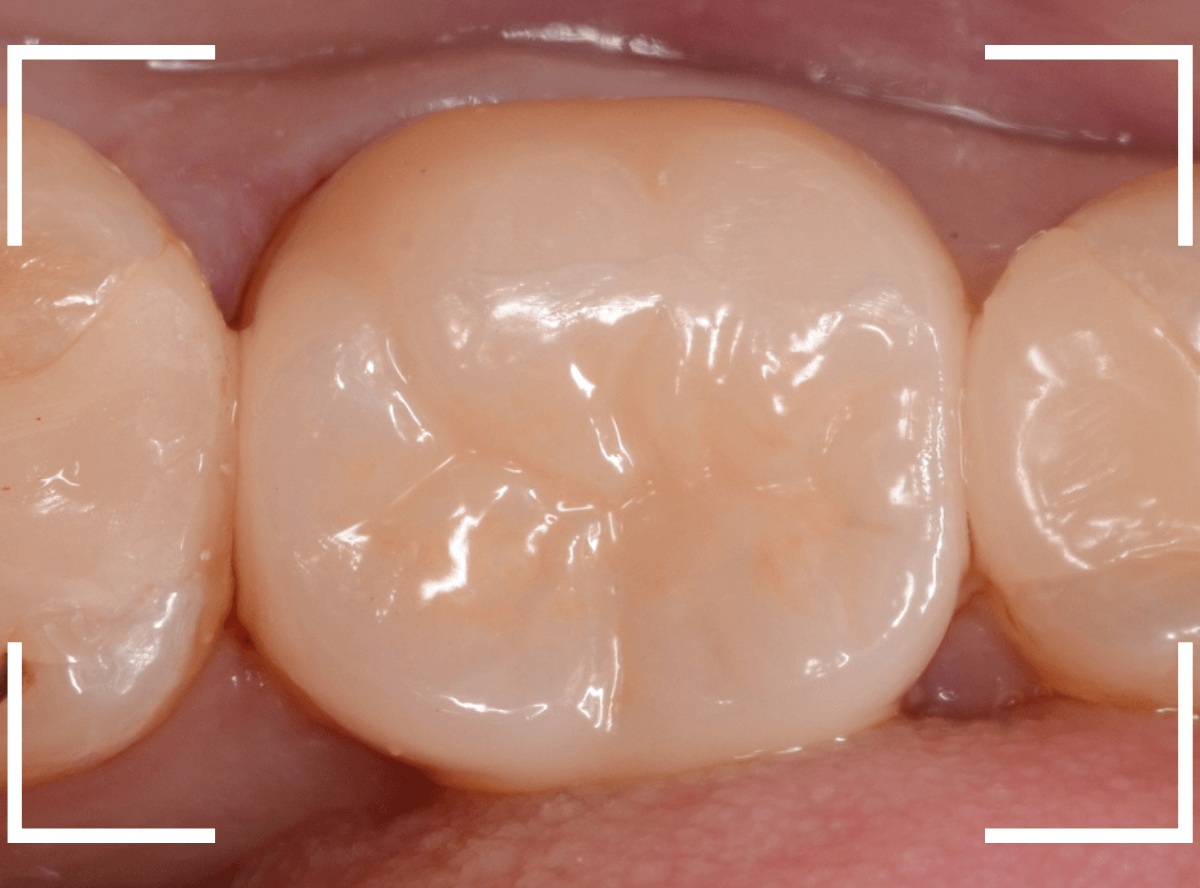

今回は、オール・ジルコニア・クラウンで製作することになりました。

最終setした状態です。

今回は厳しい条件でしたが、なんとか最終setまでする事ができました。